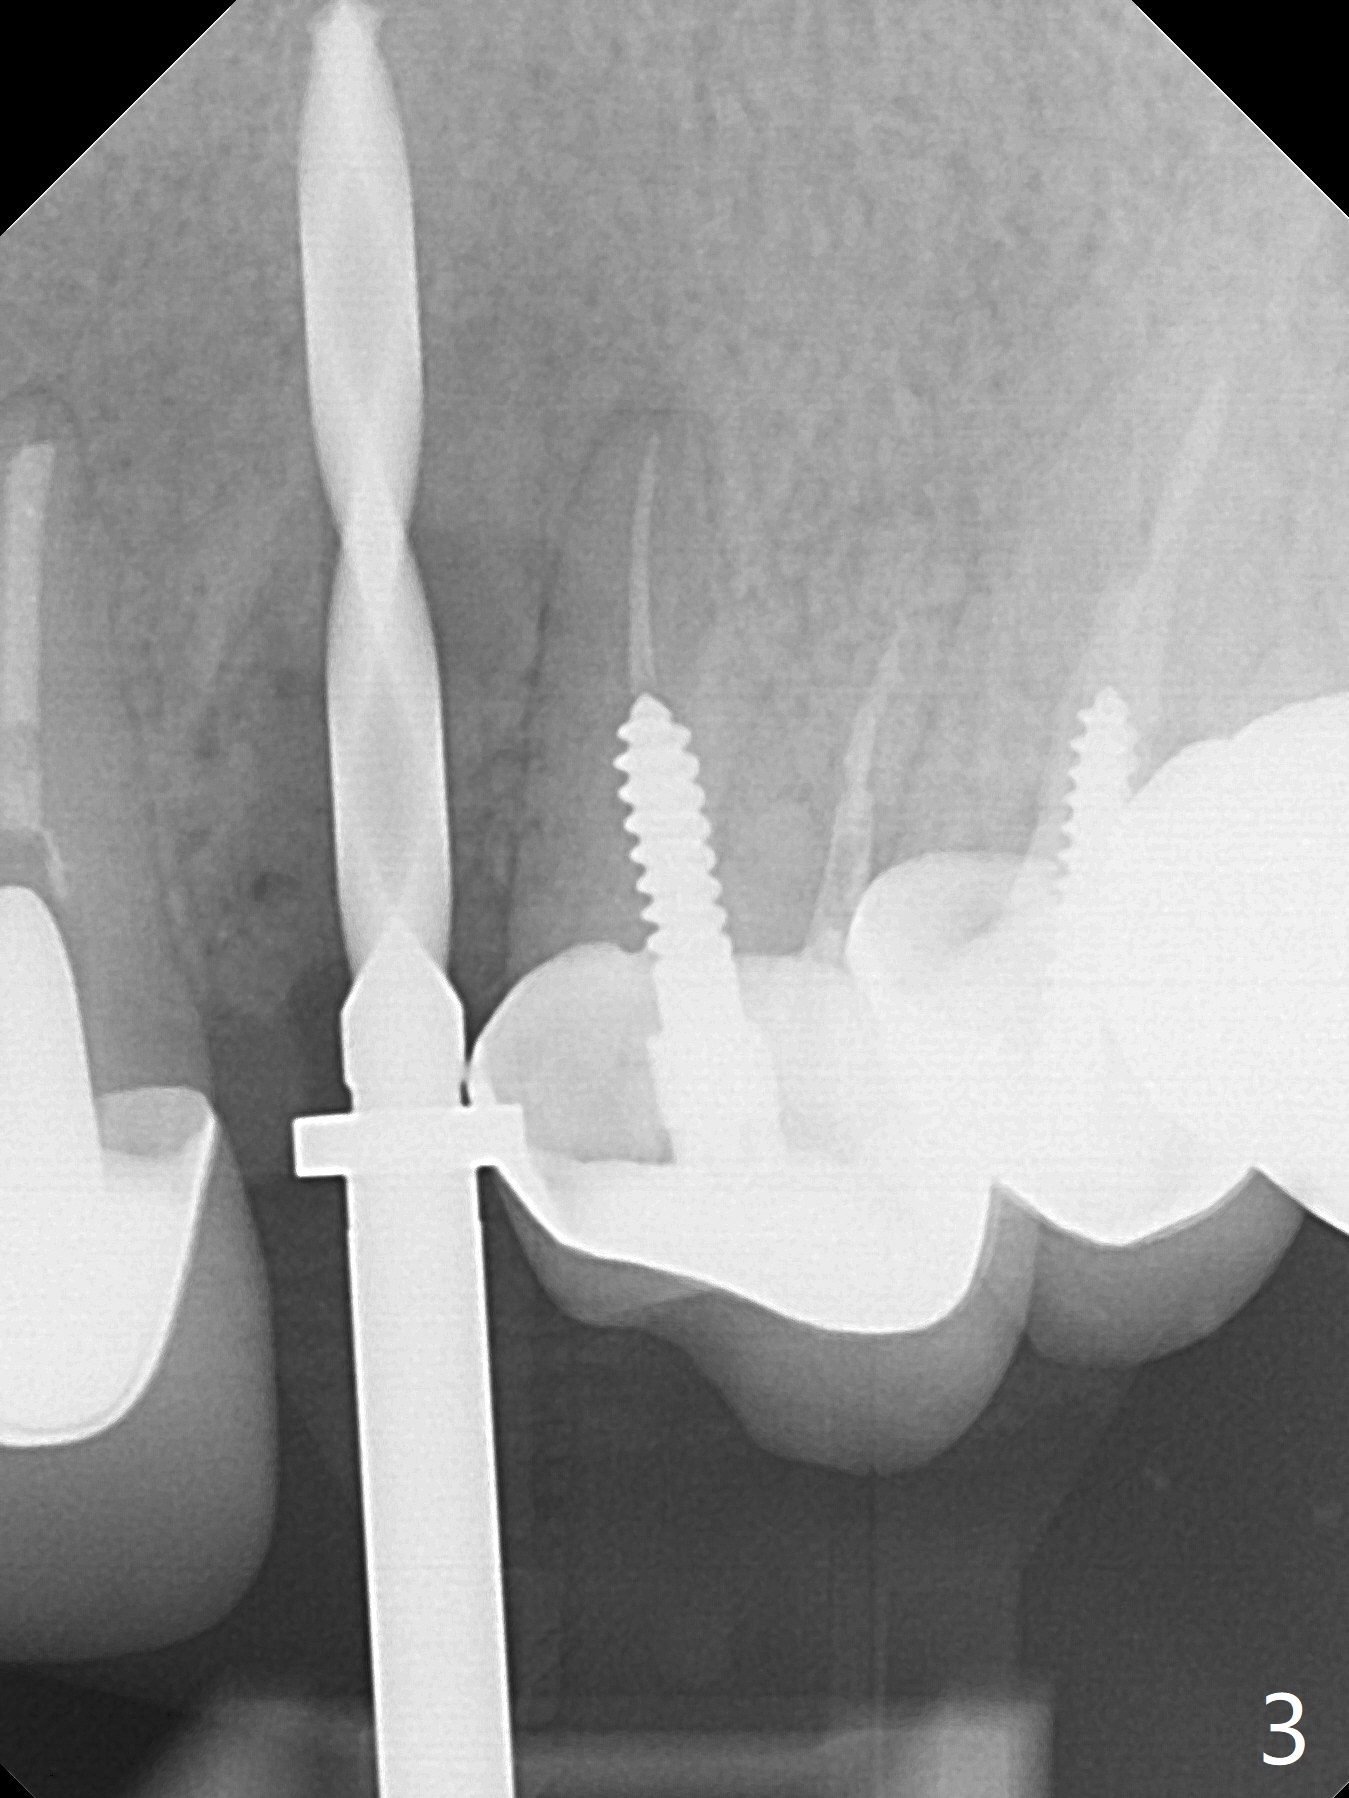

In spite of severe apical infection (Fig1,2 *), a thin narrow strip of the buccal plate (arrowheads, corresponding to the keratinized gingiva) is present when the tooth #11 is extracted. The thin bone keeps the bulging alveolus, i.e., reservoir for bone graft (Vanilla/Osteogen Fig.4 *) after placement of a 3.8x16 mm implant (Fig.3,4). A 4.5x1 mm temporary abutment, placed and trimmed for an immediate provisional, seems to be short in cuff. When an implant is placed deep to prevent periimplantitis, the cuff should be longer, i.e., 3 mm. X-ray should be taken for the depth confirmation after temporary abutment placement. Eight days postop, the mesial gingiva erythema has subsided (Fig.5 < (P: provisional)), while the apical swelling is no longer tender and most likely due to packed bone graft (*). Panoramic X-ray taken 2 weeks postop shows the clearance from the nasal cavity or the maxillary sinus (Fig.6). While the hard tissue around the implant seems to be healthy 5 months postop (Fig.7), the soft tissue is not (Fig.8). The temporary abutment is changed to a cemented one (4.5x5(2) mm) for impression (Fig.8). Since the neighboring crowns are PFM (Fig.6), the new crown will be made of the same material for shade match. Indeed PFM helps shade match in this case as well (Fig.9,10). Switching abutments (from temporary to cemented) makes it difficult to seat the crown. Post cementation X-ray leaves record for future contact loosening. The buccal gingiva remains erythematous associated with open margin (Fig.11 >) 1 year 4 months post cementation. There is no obvious bone loss 1 year 4 months post cementation (Fig.12). It appears that the crown and abutment need to be changed. Although the gingival margin remains erythematous, the gingival hemorrhage is basically lacking due to better oral hygiene during Shelter at Home (1 year 9 months post cementation, Fig.13). Change in abutment and crown will be conducted post coronavirus pandemic. In fact the abutment is incompletely seated (Fig.14 <). In addition, the tooth #12 is symptomatic with PARL associated with the buccal root (*). CBCT indicates possible buccal root fracture (Fig.15,16 ^) and loss of the buccal plate (Fig.16 <).